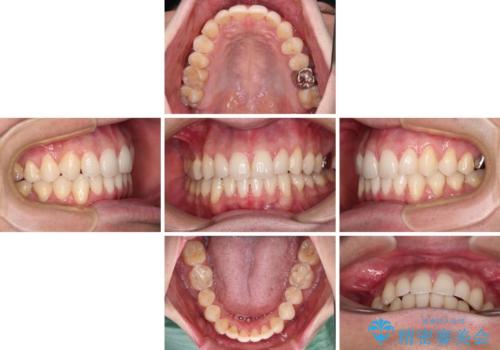

ディープバイトと叢生 インビザラインによる矯正治療

- 前歯のディープバイトと叢生を気にして来院された患者様です。

目立ちにくい装置を希望されていたため、ワイヤー装置とインビザラインを提案したところ、インビザラインを希望されました。

上下ともに叢生が認められたため、親知らずすべてを抜歯し、歯列全体を後方へ移動させることで歯列を整えることとしました。

上顎奥歯の銀歯も気になっていたので、矯正治療の途中でセラミッククラウンへ変更し、その後歯列を仕上げていくこととしました。

ディープバイトもデコボコも改善され、気になっていた銀歯もセラミックとなり、患者様には大変満足していただきました。